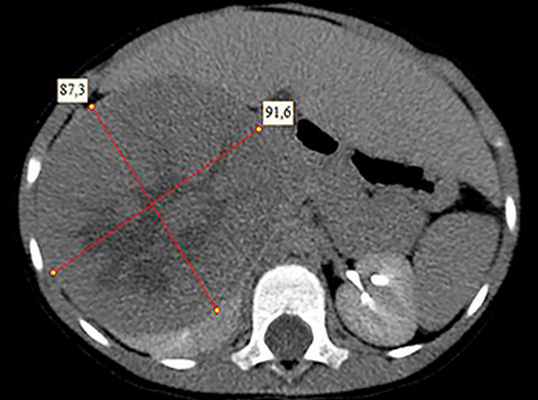

- Компьютерная томография органов брюшной полости и забрюшинного пространства с оральным и внутривенным контрастированием (см. рис. 1).

Рисунок 1. КТ брюшной полости ребенка с большой нефробластомой с метастазами в печень.

Рисунок 2. КТ: опухоль при поступлении. Клинически: при пальпации опухоль в проекции правой почки до 12 см в диаметре. Общеклинические исследования в пределах возрастной нормы. При КТ органов брюшной и грудной полости: КТ-картина объемного образования правой почки без признаков интрапульмональных метастазов (см. рис. 2). УЗИ брюшной полости: в проекции правой почки солидно-кистозное образование 101ґ114ґ99 мм, объемом 500 мл, васкуляризация активная, интактная часть почки 57ґ12ґ40 мм. Объемное образование правой почки — опухоль Вильмса. Предварительный диагноз: опухоль Вильмса правой почки, 2-я стадия.